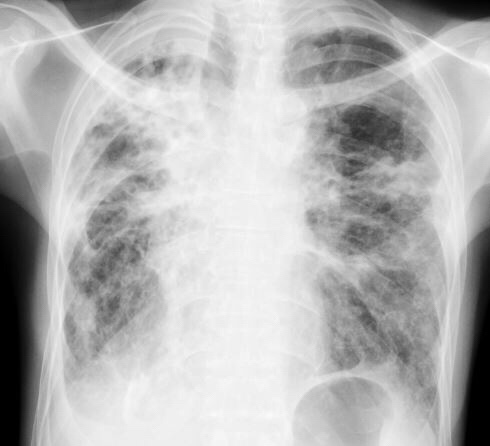

Chest X-ray showed worsening bilateral infiltrates – particularly on the right – and two courses of oral antibiotics (augmentin first followed by ciprofloxacin) produced only transient relief.

Sputum sent for acid-fast bacilli (AFB) smear was positive, and mycobacterial cultures were positive in two weeks for Mycobacterium abscessus. A repeat sputum sample yielded the same result. A CT thorax was performed, showing essentially worsening of bronchiectasis.